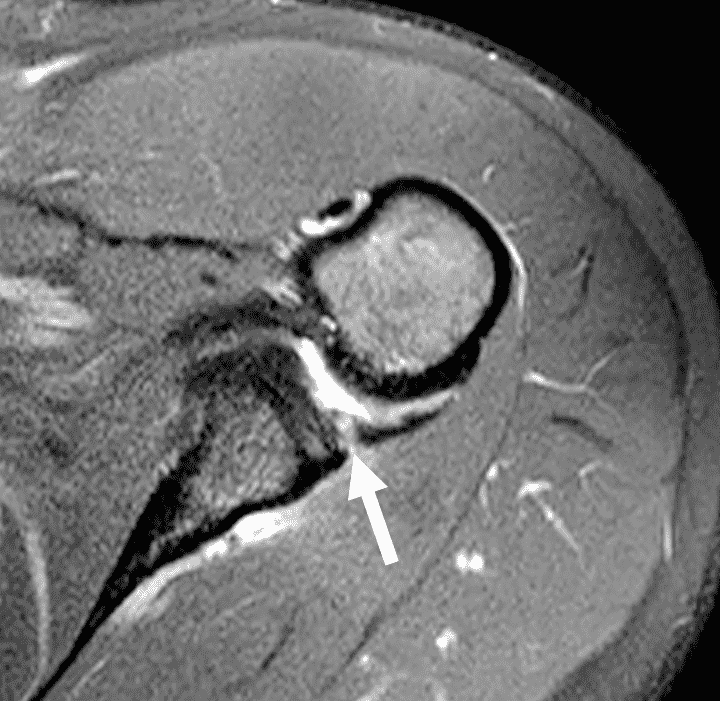

Figure 3: 18 year-old-female college softball player with acute left shoulder batting injury. (3A and 3B) Axial fat-suppressed proton-density-weighted images show a nondisplaced intrasubstance posteroinferior labral tear (solid arrows) and anteromedial humeral head impaction fracture with mild underlying marrow edema (dashed arrows).